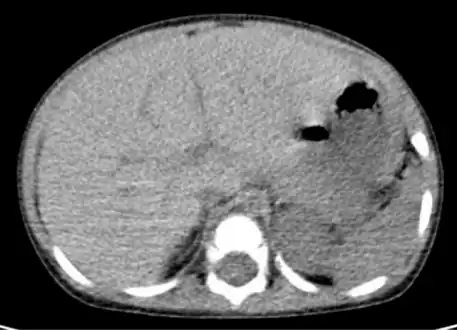

Computed tomography finding of hepatomegaly.

Computerized tomography (CT) can help to obtain accurate anatomical information, in individuals with hepatomegaly for the purpose of a complete diagnosis.[21]